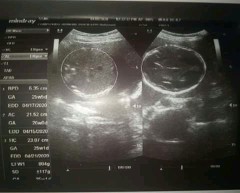

Baby Boy :)

Momshh done na po sa ultrasound suhe po sya kase 6months palang naman po . Pero iikot parin naman daw sabi ni doC. .. my naisip na po akong pangalan sa kanya kaso ayaw naman ng papa nya pati ng tiyahin ko pambabae daw kase , ang naisip ko "SEAN MEI" kayo na po humusga . Kunq pangit po give me some name sa bandang dulo , Ok naman yung SEAN eh yung MEI daw pang girl ^^ thanks po :)